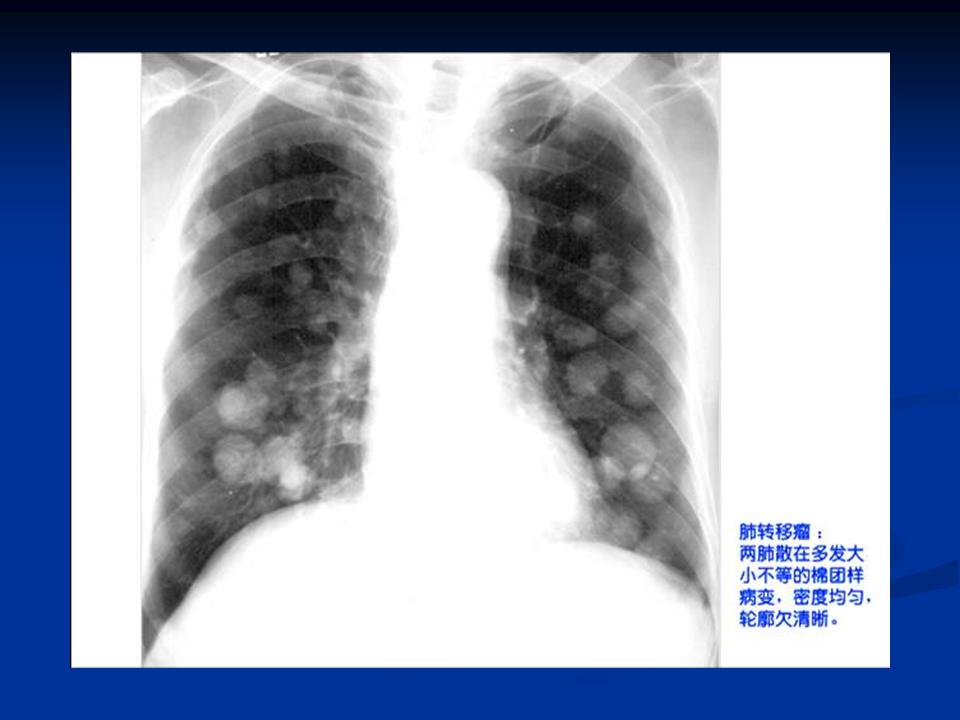

肺转移瘤与韦格肉芽肿影像鉴别